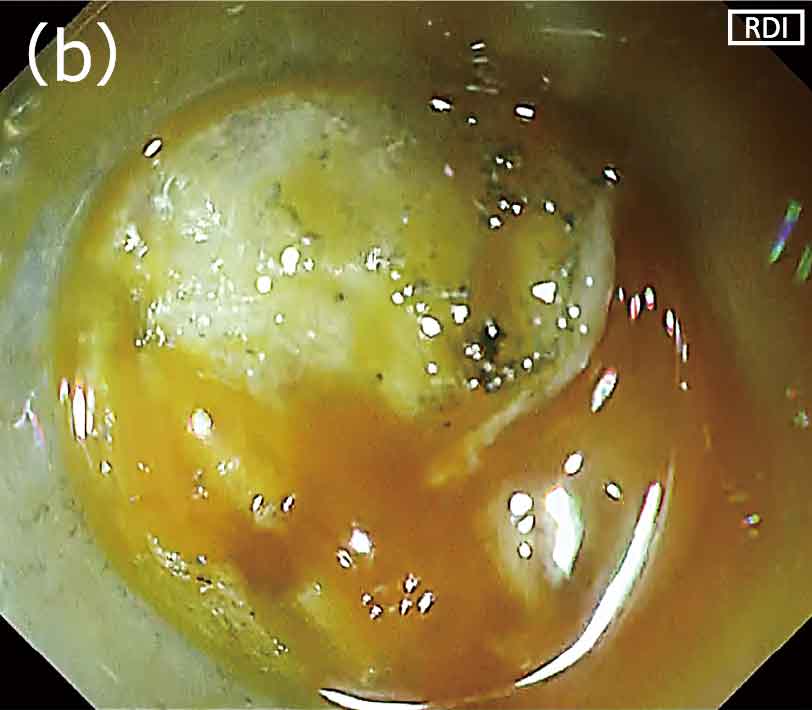

内視鏡的粘膜下層剝離術(以下、ESD)時に多量の出血が生じた場合、白色光観察では画面全体が赤くなるため、出血点の特定が困難となることがしばしばありました。出血点の視認性が低いなかでの高周波止血鉗子による凝固止血は、ピンポイントの止血操作が困難になるために治療時間の延長につながるだけでなく、過凝固による遅発性穿孔リスクを高めてしまう場合もあります。しかし、白色光観察では出血点の同定が困難な場面でも、RDI(Red Dichromatic Imaging:赤色光観察)モードに切り替えるとヘモグロビン濃度の高い出血点が濃いアンバー色として強調されますので、出血点の視認性が向上します(図1a,b)。また脂肪の多い胃の大彎側や回盲部におけるESDでは、脂肪により血管の視認性が低下するだけでなく、剝離時に脂肪がレンズに付着し視野が悪くなるため、処置がしづらくなります(図2a)。このような状態では剝離や止血処置が困難となり、処置に時間を要するだけでなく危険な状態になることがありました。しかし、RDIモードの特性により脂肪が目立たなくなり、よりクリアな視野が得られるため、処置がスムースに行えるようになります(図2b)。

〈図1〉出血点の視認性(a)白色光観察;(b)RDIモード